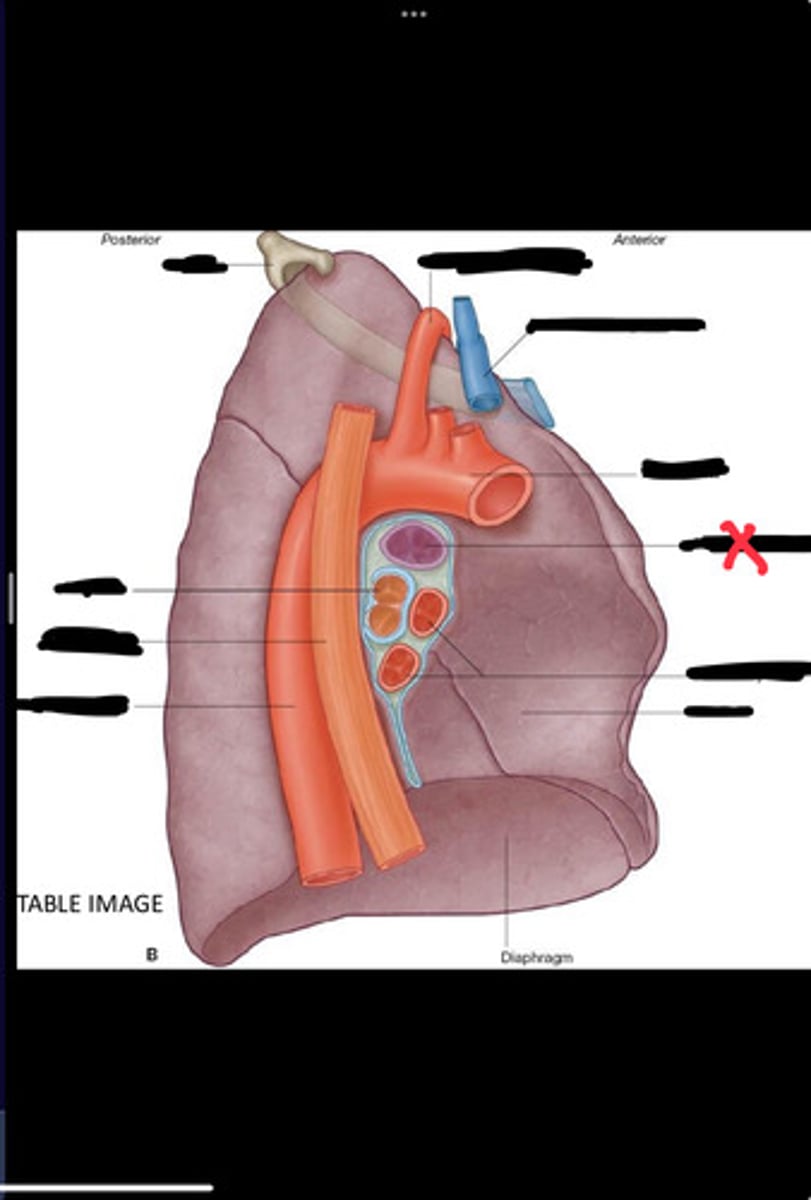

Diaphragm

Inferior vena cava

Superior vena cava

Subclavian vein

Right bracheocephalic vein

Subclavian artery

Esophagus

Bronchus

Rib 1

Left subclavian artery

Left brachiocephalic vein

Aortic arch

Pulmonary artery

Pulmonary vein

Heart

Left brachiocephalic vein

Azygos vein

Esophagus

Bronchus

Fibrous pericardium

Parietal layer of serous pericardium

Pericardial cavity

Visceral layer of serous pericardium

Junction between fibrous pericardium and adventitia

Heart

Thoracic aorta

Rib 1

Pulmonary artery

Bronchus to superior lobe